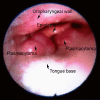

Extramedullary plasmacytoma of the tongue base